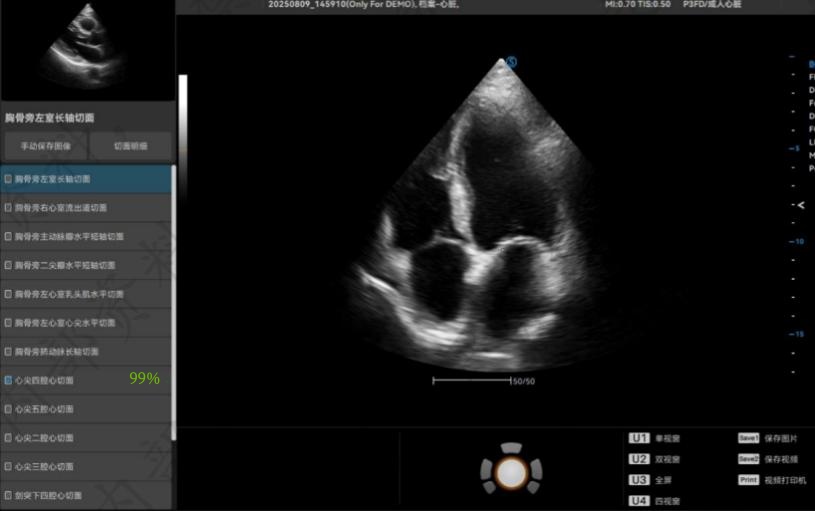

作为下沉帮扶专家,邱舜敏博士关注到基层医疗机构存在的短板与发展瓶颈,在本年度的帮扶中,认识到超声切面的准确性关系到工作效率以及诊断准确性,进而影响临床的治疗方案。为破解基层医院存在超声医师切面手法参差不齐的问题,此次创新性引入AI辅助判断心脏及胎儿标准切面自动识别、乳腺及甲状腺结节自动识别并分类等,有效地协助揭西县人民医院超声科的医师在日常工作中快速、准确地处理影像信息,辅助提高超声切面手法,并提升对疑难病例的甄别能力,缩短诊断时间,减少主观差异,使报告更加标准化、精准化。

目前AI切面标准化识别已初见成效。未来,通过专业培训、流程优化,在AI运用更加成熟的基础上,将加快其与科研相结合。